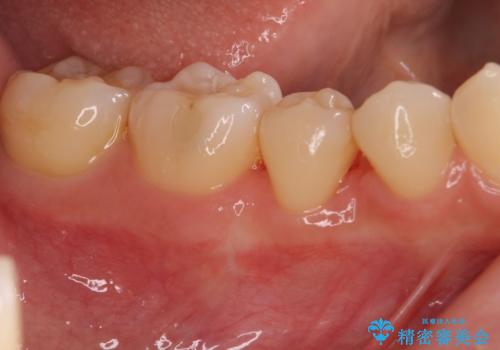

骨の再生治療手術をして10か月経過観察をしたのち、骨を平坦化する手術を行い、治療終了となりました。

・再生治療は、10か月経過観察をする必要があります。